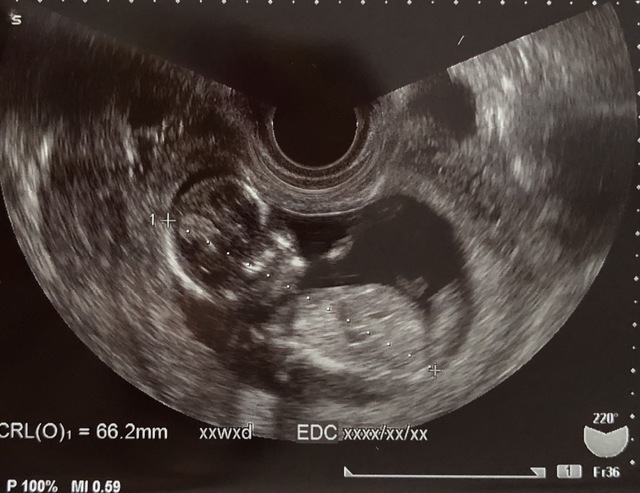

13週3日(13w3d・性別不明)|れいみ さん(25歳)

エコー写真撮影時のエピソード:

脳みその形がハート型でママ、パパ大好きだよと言っているようで幸せな気持ちになりました。

初めての出産で不安な気持ちもありますが、このエコー写真を見ると頑張ろうという気持ちになります。早く会ってママもパパも大好きだよと伝えたいです。